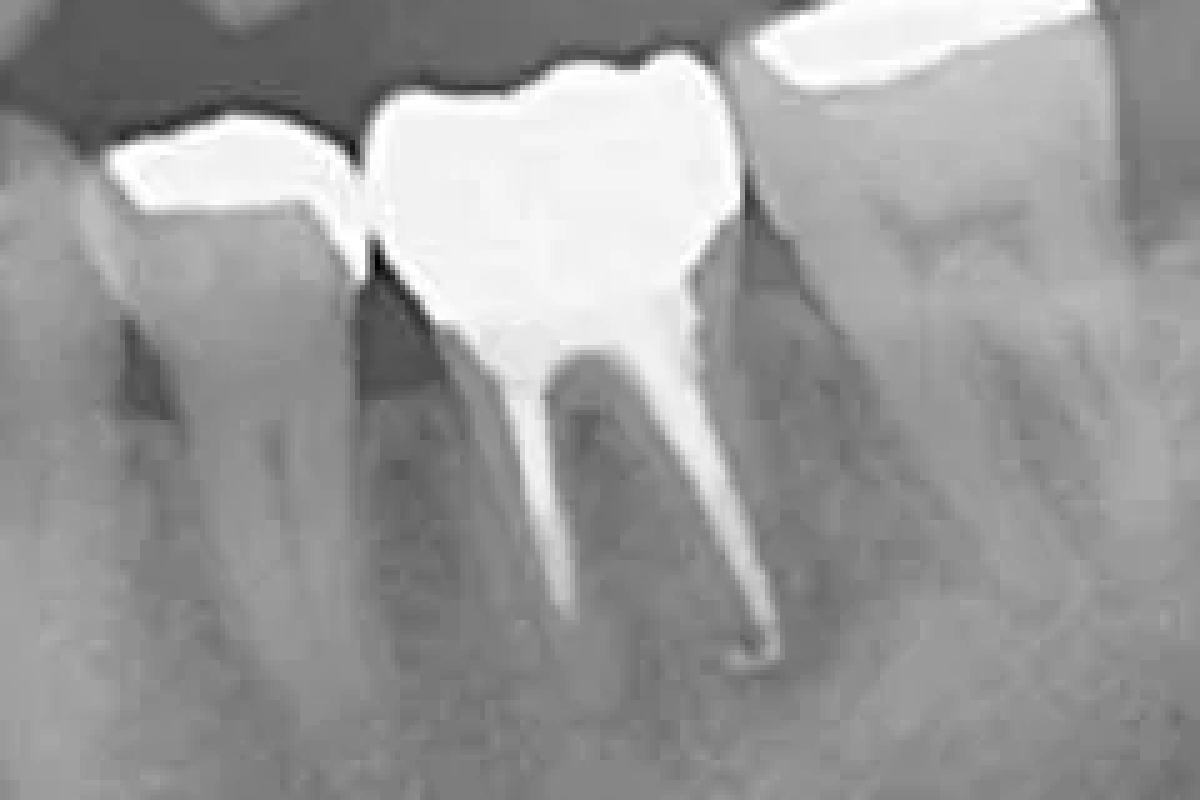

当院で処置した症例をご紹介します。

他院で抜歯と言われてしまった歯でも抜歯せずに対処した症例も多数あります。

黒い影が出ている部分が問題の個所で(根尖病巣)、治療後はこの影がなくなっているのが見て取れると思います。

After

価格は約2万円。根管を治療した症例。リスクとして、低い可能性ではあるが、再発する可能性がある。